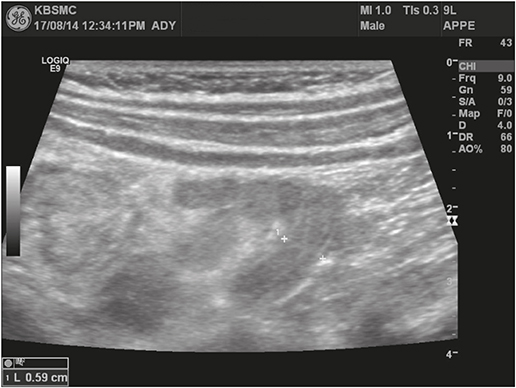

The patient was subjected to bowel sonography to exclude intussusception; with results showing no evidence of intussusception but edematous bowel wall thickening, which suggested enteritis, and a 6 mm dilatation of the appendix with wall thickening, which was suspicious of early appendicitis (Fig. 2). Intravenous antibiotics were initiated upon the suspicion of bacterial enteritis and symptomatic medication was administered for watery diarrhea and abdominal pain.

Fig. 2

Wall thickening with 6 mm of dilatation of appendix was observed on bowel sonography.